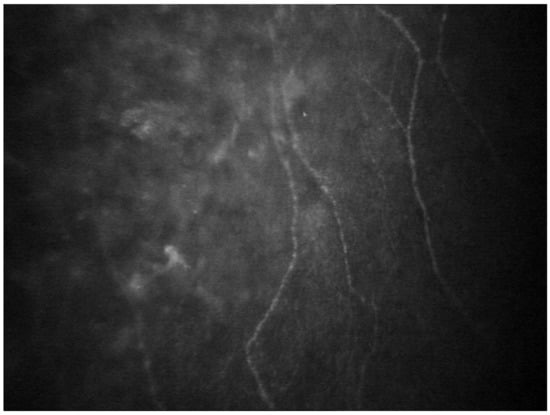

- Chorioretinal Vascular Changes

- Rousseau, A.; Terrada, C.; Touhami, S.; Barreau, E.; Rothschild, P.-R.; Valleix, S.; Benoudiba, F.; Errera, M.-H.; Cauquil, C.; Guiochon-Mantel, A.; et al. Angiographic Signatures of the Predominant Form of Familial Transthyretin Amyloidosis (Val30Met Mutation). Am. J. Ophthalmol. 2018, 192, 169–177. [Google Scholar] [CrossRef] [PubMed]

- Marques, J.H.; Coelho, J.; Malheiro, J.; Pessoa, B.; Beirão, J.M. Subclinical retinal angiopathy associated with hereditary transthyretin amyloidosis–Assessed with optical coherence tomography angiography. Amyloid 2021, 28, 66–71. [Google Scholar] [CrossRef] [PubMed]